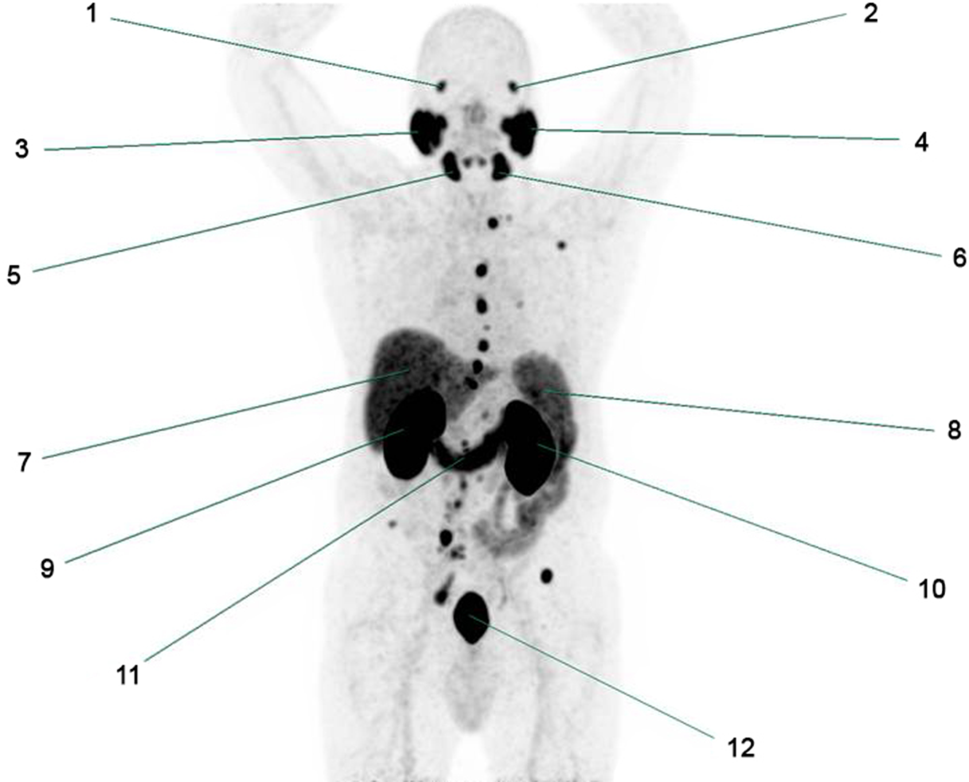

PSMA is a type II transmembrane glycoprotein, expressed by the apical side of benign prostate epithelium. The PSMA receptor is significantly overexpressed in 90% of the PCa cells and its expression tends to increase 100–1000 times with the aggressiveness of the tumor (e.g. Gleason score or extent of metastases) [11]. Since labeled PSMA tracers bind with a high affinity to the PSMA receptor, they represent an attractive target for nuclear (PET) imaging. Although its specific role has not been clarified yet, the protein contributes to glutamatergic neurotransmission and folate absorption [12]. PSMA is also physiologically expressed in the salivary and lacrimal glands, kidneys, central nervous system, duodenum and colon as shown in Fig. 1 [13].

Fig. 1

Frontal image of 68Ga-PSMA Maximal Intensity Projection (MIP) representing the uptake of PSMA in healthy tissue in a patient suspected for PCa metastases. All numbers represent healthy tissue. Non-specified areas with high activity are suspected for PCa metastases. 1. Right lacrimal gland, 2. Left lacrimal gland, 3. Right parotid gland, 4. Left parotid gland, 5. Right submandibular gland, 6. Left submandibular gland, 7. Liver, 8. Spleen, 9. Right kidney, 10. Left kidney, 11. Duodenum, 12. Urine bladder